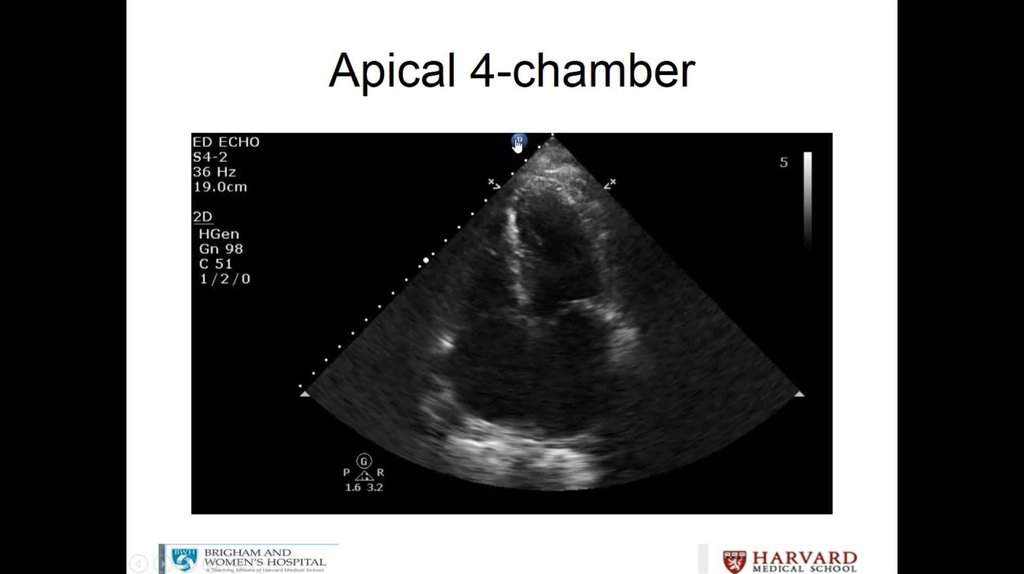

Litrasound in the ICU: What Every Intensivist Should Know